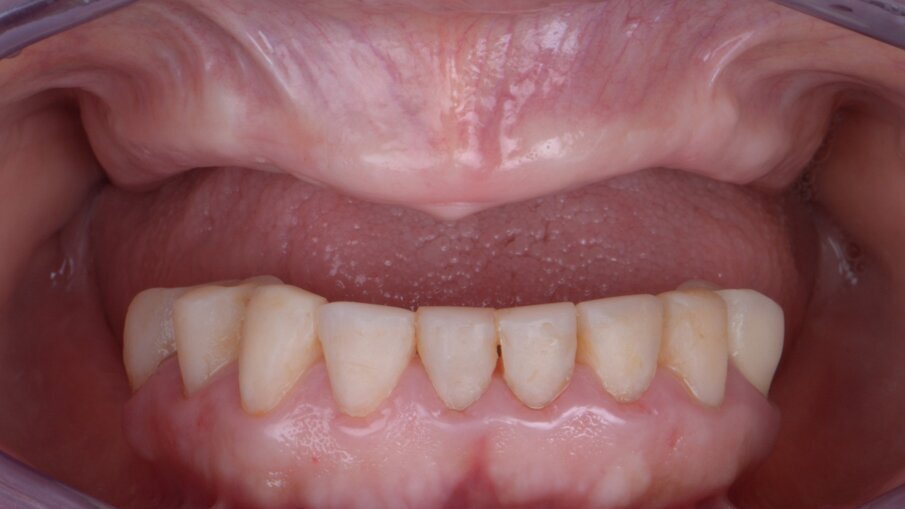

Veniamo quindi al posizionamento della protesi mediante carrier, a sua volta ancorato agli stessi punti di fissaggio della dima base. È significativo osservare come la stabilizzazione della sola vite palatale consenta l’allineamento perfetto tra i sistemi di fissaggio (Fig. 22), mentre il dettaglio mostrato in Fig. 24 illustra efficacemente come prima della cementazione della protesi l’accoppiamento e la centratura del foro protesico appaiano perfetti, confermando quindi come l’obiettivo di alloggiamento della protesi nella sede prestabilita sia stato colto. Per la fase di cementazione con cemento duale si è prestata attenzione alla realizzazione di un foro aggiuntivo per permettere al materiale di raggiungere gli abutment. I fori di accesso alle viti vengono tappati con filo di teflon (Figg. 25, 26) ed è a questo punto possibile andare a fissare la protesi e rimuovere il sistema carrier (Fig. 27). Lasciamo la dima in posizione, così che nell’eventualità in cui un abutment non dovesse essere stato cementato correttamente, ci riserviamo la possibilità di riprendere il posizionamento strategico dell’intero sistema Pcube, intercettando possibili impedimenti alle manovre di finalizzazione del caso.

Nella fase di controllo finale possiamo apprezzare come i rapporti di intercuspidazione programmati siano stati perfettamente rispettati (Fig. 28), senza necessità di ricorrere a procedure di auto-centratura della protesi, grazie ad una attenta pianificazione digitale. Eseguiamo una scansione con scan abutment in posizione prima di procedere con la rimozione della dima base e il fissaggio della protesi (Figg. 29-31). Controlliamo le possibilità di mantenimento igienico tenendo conto che, trattandosi di un intervento flapless, non abbiamo le problematiche legate alla gestione di una linea di incisione (Fig. 32). La Fig. 33 mostra la corretta guarigione dei tessuti quindici giorni dopo il trattamento. Eseguiamo un controllo radiografico mirato a verificare il corretto alloggiamento di tutti gli impianti e della protesi (Fig. 33), dove possiamo vedere la struttura di rinforzo in fibra di vetro.